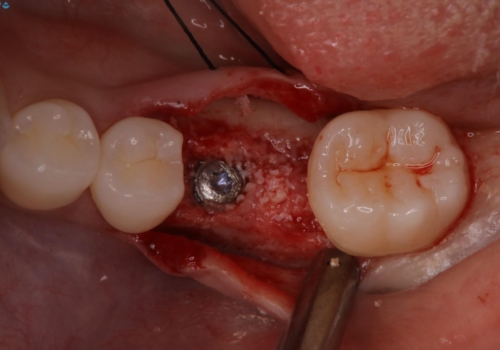

- 他院で抜歯と言われ、今後どうしたらいいのかを相談された患者様です。

抜歯を行った後は、Br、義歯、インプラント、何もしないという選択肢のメリットデメリットを説明させていただき患者様がインプラント治療を希望されたので今回治療させていただくことになりました。

歯のなかったところをインプラント治療を行うことによってまた噛める喜びを感じていただけて良かったと思っております。